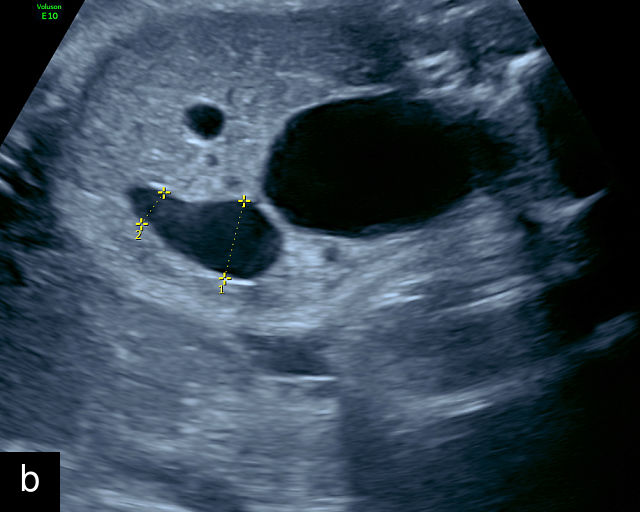

There are three types of vasa previa.30,262 In Type 1, the cord inserts into the membranes rather than the placenta. Unprotected vessels then traverse the membranes over the cervix to insert into the placenta (Figure 21a; Video 12). In Type 2, unprotected vessels running through the membranes over the cervix connect the main placental lobe with an accessory lobe (Figure 21b).263 In Type 3, there is generally a normal placental cord insertion, and unprotected vessels exit one placental edge, run through the membranes over the cervix and then boomerang to insert into the placental edge at another site (Figure 21c).25,28,29,264 Regardless of the type, all these expose the fetus to the same risks.

21